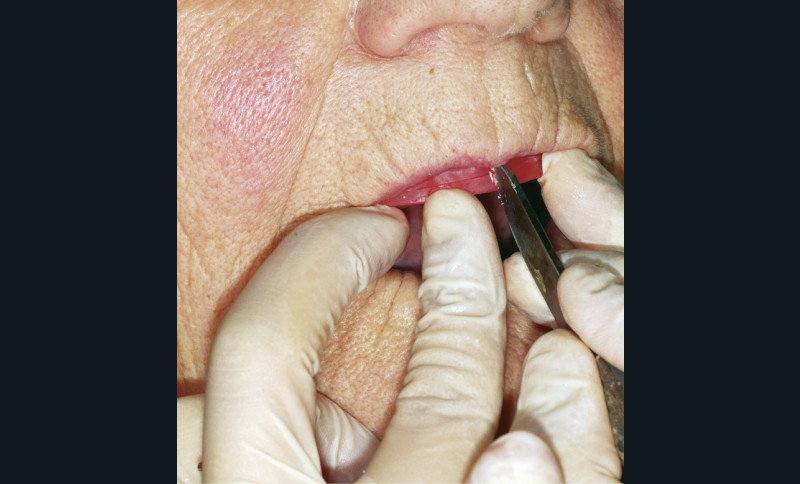

Au niveau phonétique, on teste les phonèmes /f/ et /v/ en faisant prononcer « feu » et « veu » de manière prolongée : le bord vermillon de la lèvre mandibulaire doit se trouver en contact avec les futures incisives maxillaires (fig. 10). Le réglage de la fonction doit conforter le réglage esthétique (fig. 11).